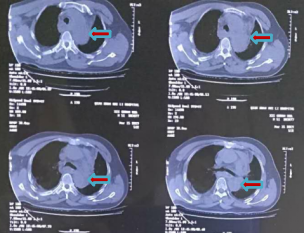

外院胸部CT:主动脉壁增厚

主动脉CTA:主动脉弓降主动脉处破口,近端破口直径约7.6mm